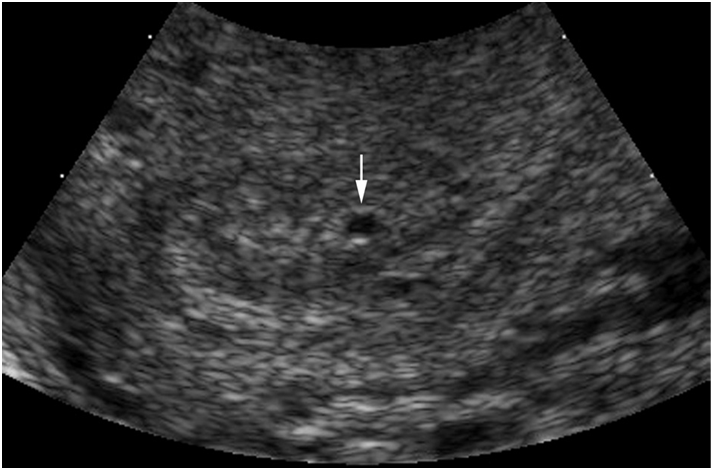

Type B: lớp dịch lòng tử cung có hình ảnh là nang echo trống, bờ đều đặn. Hình ảnh này gặp ít hơn hình ảnh type A (tỷ lệ < 25%).

Nghiên cứu cũng ghi nhận tỷ lệ thai ngoài tử cung có hình ảnh ứ dịch lòng tử cung type B nhưng không kèm theo khối echo hỗn hợp hay hình ảnh túi thai nào ở cạnh buồng trứng là 0,9%. Vì vậy với tỷ lệ thai ngoài tử cung trong dân số chung là 2%, nghiên cứu đưa ra một tỷ lệ ước tính như sau: ở một bệnh nhân có xét nghiệm thai dương tính, siêu âm không ghi nhận khối echo hỗn hợp nào ở cạnh buồng trứng và kèm theo là hình ảnh cấu trúc dịch lòng tử cung type B (echo trống, bờ đều đặn) thì khả năng thai ngoài tử cung là 0,9%x2% # 0,02%, khả năng thai nằm trong tử cung khá cao 99,98%.